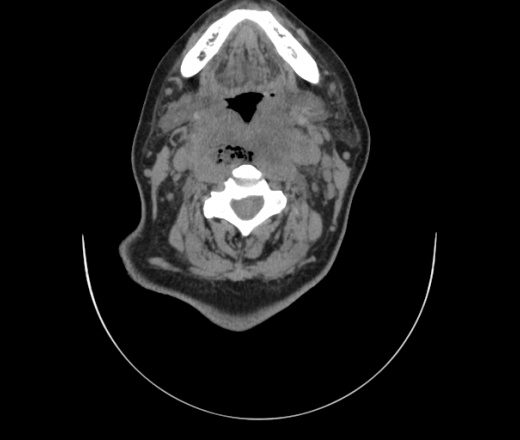

Женщина поступила в х/о спустя 4 дня после того как при употреблении карася подавилась костью.

Наличие газа в средостении на протяжении тел С2-С6 (медиастинальна эмфизема); рыбная кость на уровне тела С6.

При всем уважении, но говорить о медиастинальной эмфиземе, оценивая мягкие ткани шеи, как-то слишком резко. На мой взгляд, это ретрофарингеальное пространство.

Эвакуировали почти 100мл гноя. Но кость не смогли найти. Думаю что она даст дальнейшее ослоднение. Эндоскопически за черпалонадгортаной звязкой не смогли зайти в пищевод, все мягкие ткани отечные, просвет пищевода сдавлен. По всей видимости параэзофагеальная клетчака тоже задействована. Эмпиема, если ее можно так назвать, незнаю как правильно дошла до уровня яремной вырезки. Чем закончиться напишу. Ждем медиастинита.

Флегмона заглоточного пространства шеи, только операция, флегмоны вскрывают. Риск медиастинита.

Согласен с Вами; конечно, наличие газа в клетчатке ретрофарингеального пространства (затмение с опечаткой..). К сожалению, процесс "продвигается" к медиастиниту. Но почему никто, не отмечает наличие рыб. кости; или это для Всех очевидно?

Так вы уже отметили. Хотя ориентировал бы не скелетотопически, а на перстнечерпаловидный сустав.

Кость то мы сразу выявили, размеры где то 17*2мм, но ее так и не получается найти в этой каше